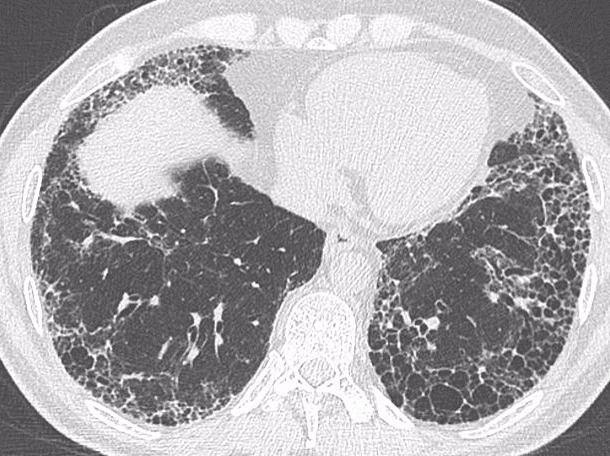

Figura 1A e B: Paciente com fibrose pulmonar idiopática mostrando franca progressão da doença nos exames de imagem de seguimento com diferença de 1 ano. Note a maior extensão do reticulado, bronquiectasias, bronquiolectasias e do faveolamento em B.

Em pacientes com FPI, a progressão radiológica geralmente se manifesta com aumento na extensão do padrão de pneumonia intersticial usual (PIU), tanto no plano axial como longitudinal, geralmente acompanhado do aumento no tamanho e quantidade de cistos de faveolamento. Além disso, o aumento na quantidade de bronquiectasias e bronquiolectasias de tração demonstrou ser um fator preditor de mortalidade na FPI(2). Em pacientes com outras doenças intersticiais pulmonares, o padrão de progressão pode ser variável, incluindo evolução das opacidades em vidro fosco para alteração reticulares ou evolução do reticulado para cistos de faveolamento, podendo se associar a aumento na extensão das bronquiectasias e bronquiolectasias de tração. Pacientes com padrão de pneumonia intersticial não específica (PINE) podem progredir para um padrão semelhante a PIU, por exemplo(3).